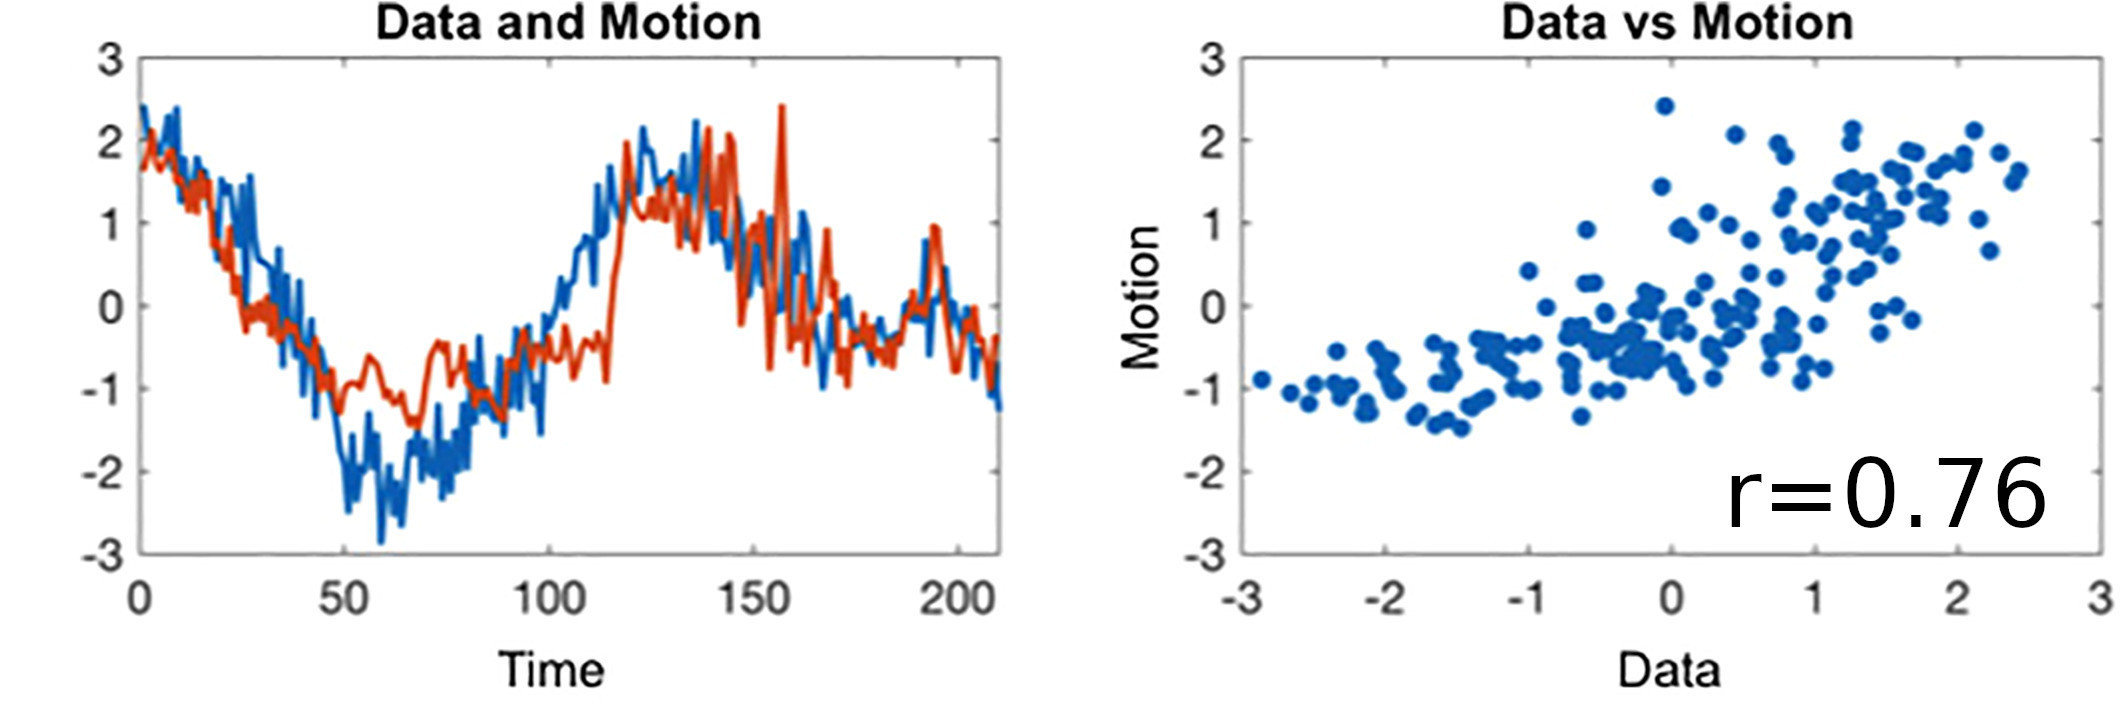

BH-induced CVR: Issues

Two problems:

- There's a measurement delay, and regional variations of the physiological delay

- The BH task presents collinear motion to signal of interest

Motion

CO2

BOLD

BH-induced CVR: Issues

Two problems:

- There's a measurement delay, and regional variations of the physiological delay

- The BH task presents collinear motion to signal of interest

Motion

CO2

BOLD